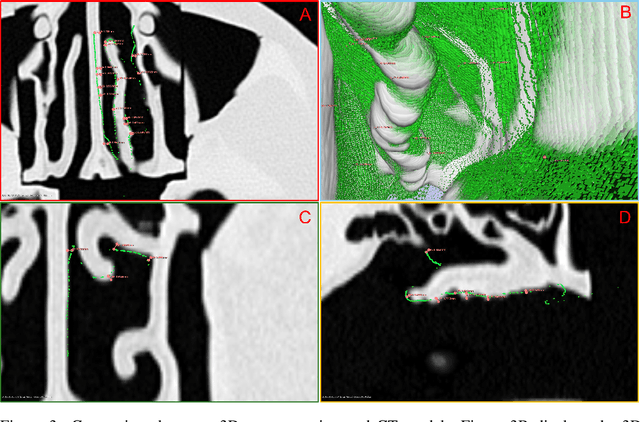

Abstract:The 3D reconstruction of the surgical field in minimally invasive endoscopic surgery has posed a formidable challenge when using conventional monocular endoscopes. Existing 3D reconstruction methodologies are frequently encumbered by suboptimal accuracy and limited generalization capabilities. In this study, we introduce an innovative pipeline using Neural Radiance Fields (NeRF) for 3D reconstruction. Our approach utilizes a preliminary NeRF reconstruction that yields a coarse model, then creates a binocular scene within the reconstructed environment, which derives an initial depth map via stereo vision. This initial depth map serves as depth supervision for subsequent NeRF iterations, progressively refining the 3D reconstruction with enhanced accuracy. The binocular depth is iteratively recalculated, with the refinement process continuing until the depth map converges, and exhibits negligible variations. Through this recursive process, high-fidelity depth maps are generated from monocular endoscopic video of a realistic cranial phantom. By repeated measures of the final 3D reconstruction compared to X-ray computed tomography, all differences of relevant clinical distances result in sub-millimeter accuracy.